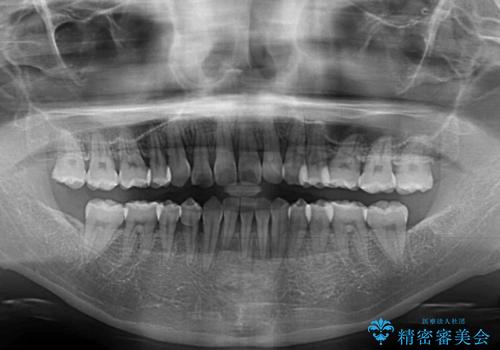

通常であれば、上下顎左右小臼歯各1歯の合計4本を抜歯しますが、歯肉退縮の著しい下顎前歯を抜歯して欲しいという患者様の強い希望により、上顎のみ左右小臼歯2歯を、下顎は前歯を1歯を抜歯することとしました。

抜歯する歯を変更したため奥歯の咬合はアンバランスとなりましたが、前歯は綺麗に整い、歯肉退縮も回避できました。